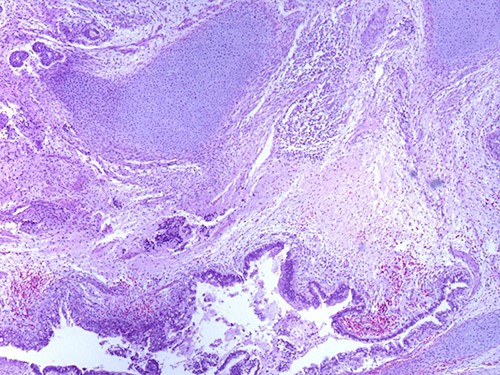

A 46-year-old woman, without clinical antecedent, presented with a tumor in the inner side of the left cheek which had rapidly grown for 3 weeks. Physical examination revealed an ulcerating mass measuring 4 × 3.5 cm, well-circumscribed, fleshly, with a white surface. There was submandibular lymphadenopathy, ranging in dimension from 1 to 1.5 cm in diameter. Magnetic resonance imaging (MRI) scan revealed the tumor of the cheek without mandibular bone infiltration or sinonasal involvement (Fig. 1). Chest computed tomography and abdominal ultrasound scan were unremarkable. An excisional biopsy was performed. Pathological examination showed a neoplastic proliferation composed of mixture of mature benign epithelial components, such as intestinal type, respiratory and squamous epithelia, and mature mesenchymal components, such as muscular tissue and cartilage (Fig. 2) and neuroglial tissue. In addition, immature and malignant tumor components were found such as small blue tumor cells resembling primitive neuroectodermal tumor (Fig. 3), adenocarcinoma and sarcoma with muscular and cartilaginous differentiation (Fig. 4). This tumor infiltrates the skeletal muscle with free margins. Immunohistochemically, epithelial components were positive for pankeratin; mesenchymal components showed desmin, myogenin and S-100 positivity and the primitive neuroectodermal tumor component was positive for NSE, CD99, GFAP, synaptophysin and focally for chromogranin. SALL4 was negative. The resected submandibular lymph nodes were devoid of malignant infiltrate. The diagnosis of TCS was established and the patient was treated by combined chemotherapy (cisplatine +5 fluorouracil) and radiation therapy. No recurrence was noted 6 months after treatment.

Mature glandular components with cartilage (magnification at ×40).